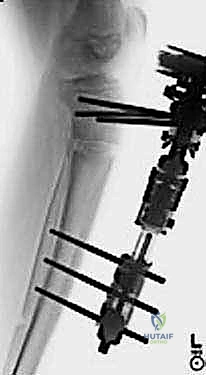

15. On the 14th day, a radiograph should show that the ends of the osteotomized tibia are separated by a distance of about 7 mm (

TECH FIG 4C,D

).

16. Angular correction can now begin. The patient is taught to place the Allen wrench into the primary angulation screw and turn 90 degrees in the direction for angular correction. This 90-degree turn will correct

---

A

B C DE

F

--- TECH FIG 4 • A. The lengthening device is applied. B. A sterile dressing is applied. C,D. Radiographs are taken to verify that there is distraction at the osteotomy site prior to correcting angulation. E,F. Correction is performed until the angulation has been recitified.TECHNIQUES 1 degree of angular deformity and can comfortably be performed four times a day for a correction of about 4 degrees per day until the deformity is corrected (

TECH FIG 4E,F